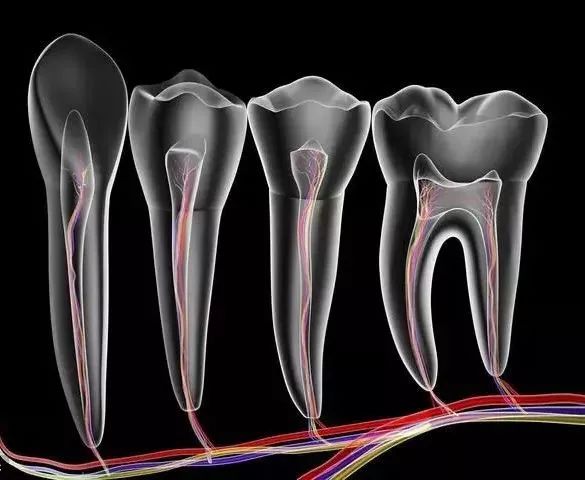

这是目前最有效、最常见的治疗牙髓病和根尖周病的方式,可以消除牙齿内部炎症及其病变源,预防炎症加重扩散,从根本治愈。

其过程就是先将牙齿内部坏死的牙髓清理干净,再放入永久性消炎杀菌的药物,最后进行冠修复来拯救这颗牙齿。

第一步:开髓

先在牙齿上开一个直通内里、 方便操作的大门。

第二步:杀神经

出了问题的牙神经会在牙齿内部腐坏、发酵,造成严重的感染和疼痛。

所以,我们需要将牙神经杀死,然后和坏死的组织一起清理出来,来消除炎症。

第三步:填充

放入永久性消炎杀菌的药物,对根管进行严密填充,保证根管之后不会再出现炎症。

最后给牙齿做一个全瓷/烤瓷牙冠,起到保护作用,同时也解决了牙齿颜色灰暗的问题,更加美观。